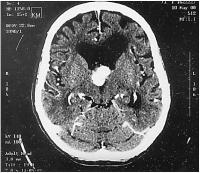

Hypernephrom-Metastase

Abbildung 4: Restläsion 12 Monate nach Radiochirurgie

Keywords:

Hypernephrom

,

Magnetresonanztomographie

Metastase

Neurochirurgie

Radiochirurgie